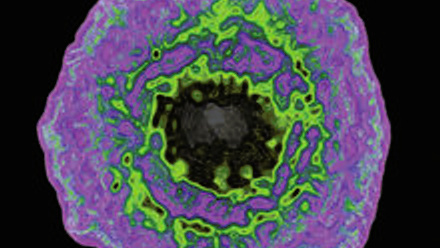

This issue of Microbiology Today is a ‘virology special’; this is in part to recognise the contribution of this year’s SGM Prize Medal winner, Harald zur Hausen, and his ground-breaking contributions to understanding the link between viruses and cancer.